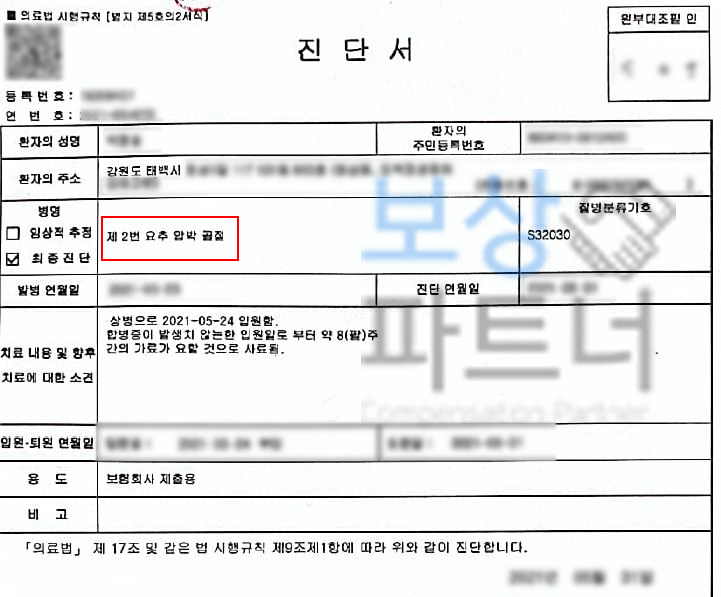

소개해드릴 박@@님은 강원 태백시 거주하시는 50대 여성분이셨습니다. 자택에서 스트레칭을 하시던 중 의자에서 넘어지셨는데요, 위 단순한 사고로 허리에 극심한 통증을 호소하셨고 병원에 내원하여 정밀검사 받아보니..

제2번 요추압박골절 S32030 진단받아 허리 보조기 착용하는 보존적 치료 시행해야 했습니다. 최소 8주간 안정을 취해야 하셨는데요, 가정에서 주부이시기도 했지만 일을 하시기도 하셨기 때문에

경제적인 손실도 크셨습니다.